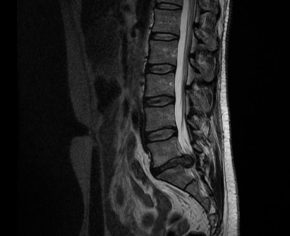

The disc herniation can be defined as the displacement of the intervertebral disc beyond the margins of the vertebral body. When a disc ring becomes weaker and breaks, it allows the “soft stuffing” to come out. The part that comes out can squeeze one of the nerves that leave the marrow, causing pain in the area of the leg that belongs to that nerve, weakness in certain muscles and tingling or numbness.

There are several techniques for the treatment of herniated disc: the minimally invasive surgery for lumbar discectomy, endoscopic surgery of the lumbar spine, if performed in appropriate patients with a correct surgical indication and once the conservative treatments are exhausted, it is demonstrated that it has associated a high percentage of success.

The stenosis of the lumbar canal originates from an abnormal narrowing of the spinal osteon-ligamentous anatomical structures of the canal, lateral recesses or intervertebral foramina. This narrowing can affect one or more levels and can affect the whole or a part of the canal. The ECL etiology is closely correlated with the lumbar degenerative process and is classified as congenital or developmental, acquired and combined.

The clinical symptomatology of this process is characterized by repeated episodes of low back pain and radiating pain to the lower extremities, in the form of neurogenic claudication or radiculopathy.